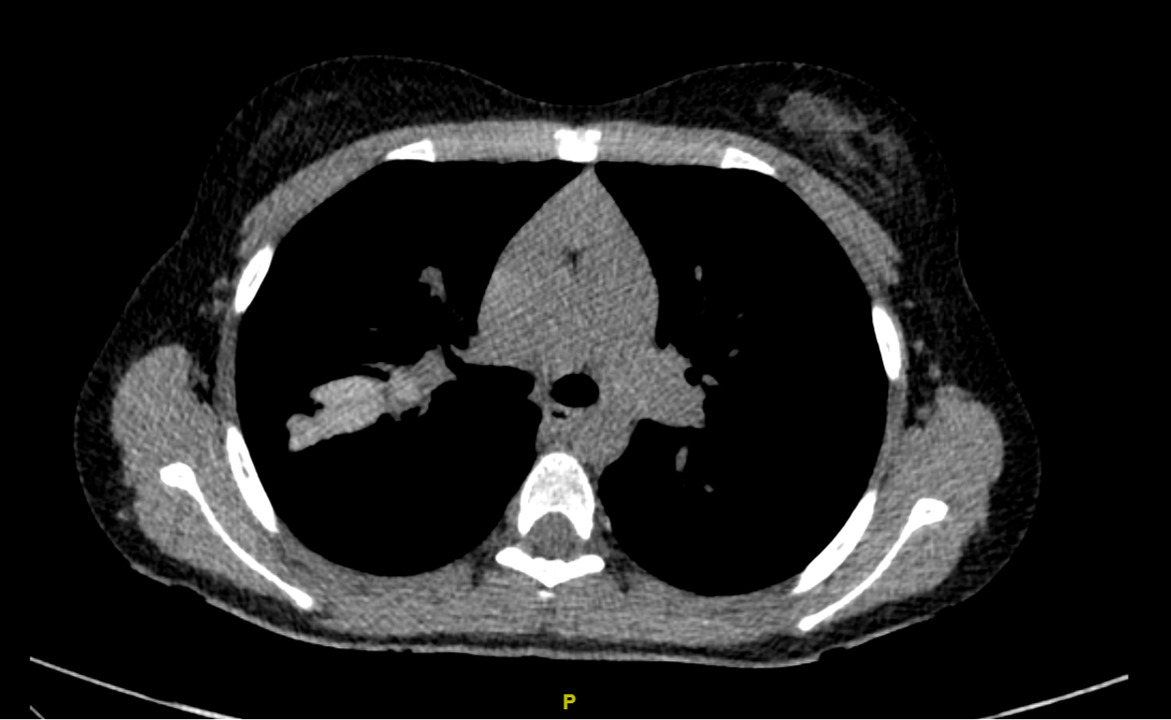

La plus grande sensibilité du scanner thoracique (le plus souvent non injecté) pour détecter des anomalies précoces à des doses de radiations ionisantes réduites (scanner low dose ou ultra low dose) a relégué au second plan la radiographie thoracique.4 Plusieurs types d’anomalie sont visibles sur les scanners thoraciques des patients, et ce dès le plus jeune âge  : DDB et épaississement des parois bronchiques, impactions mucoïdes, zones de trappage aérique, atélectasies. Certaines de ces anomalies sont réversibles sous traitement par modulateur de CFTR tel que la triple combinaison par elexacaftor-tezacaftor-ivacaftor (fig. 1).